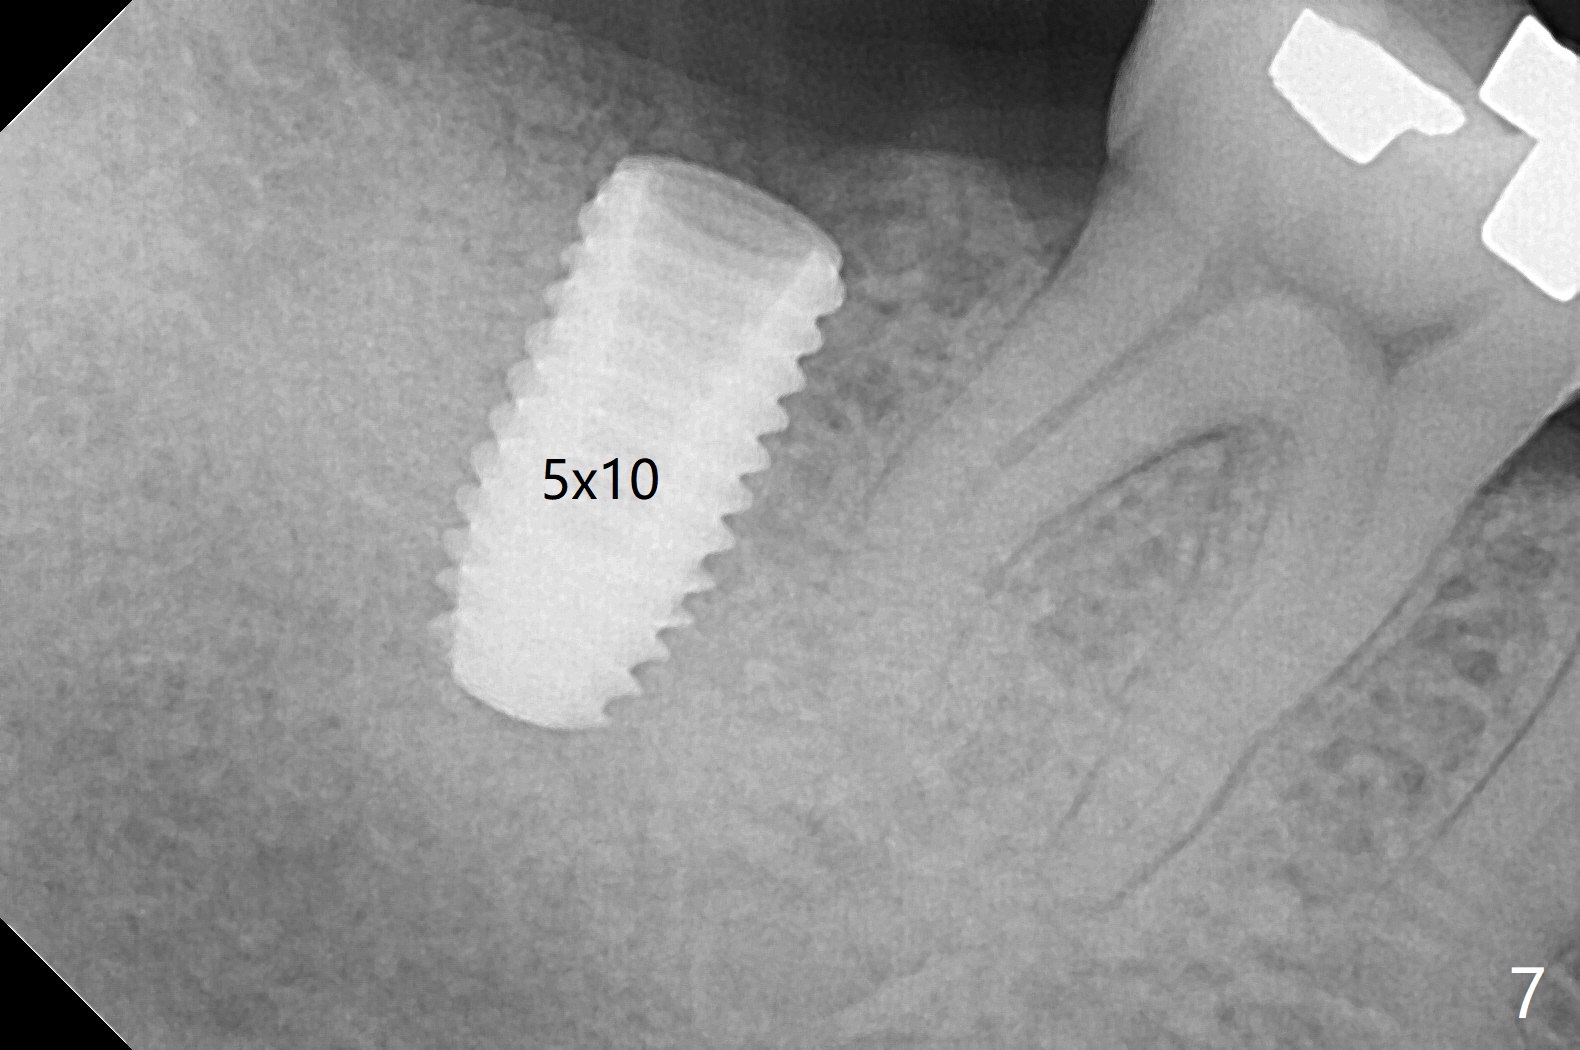

CBCT shows thin cortical bone formation mesiodistally 6.5 months post socket preservation with allograft with PRF at #31 (Fig.3 ^, as compared to Fig.1). The socket appears to be closing buccolingually 10 months postop (Fig.6 arrowheads, as compared to Fig.4). Bone density increases from 1100 units to 1,200-1,400 units 6.5 to 10 months. With underprep (4 mm), a 5x10 mm implant is placed with ~ 50 Ncm with guide (Fig.7). Following a 5.5 mm profile drill, a 5.5x3 mm healing abutment is placed (Fig.8); the implant plateau appears to be supported by the graft bone (*). The implant remains subcrestal 4 months postop (Fig.9).